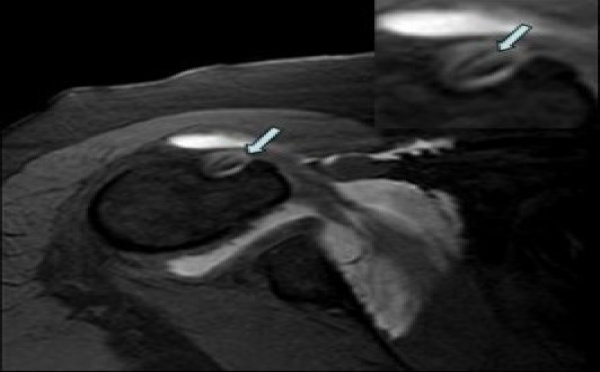

L'épaule

Entésopathie calcifiante de l’épaule

Un diagnostic = 2 coupes...